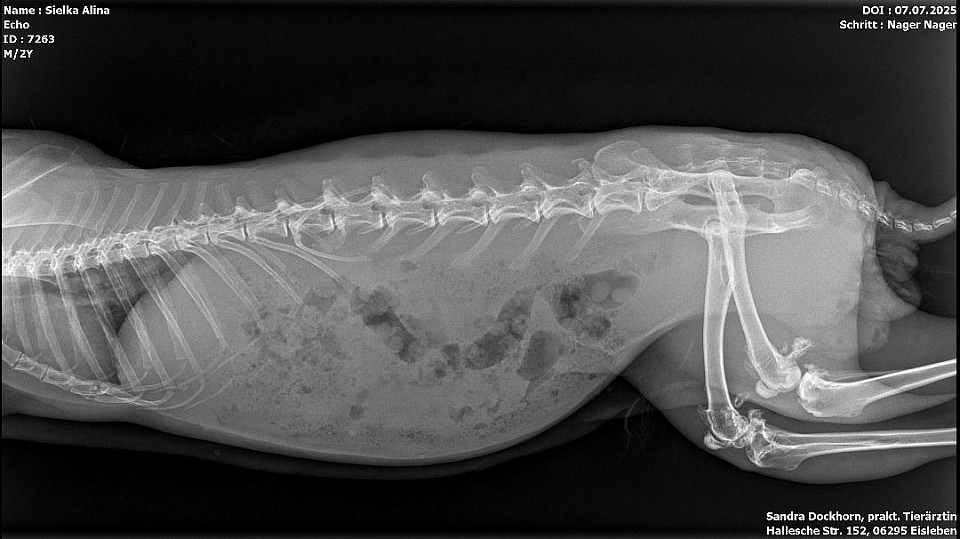

Röntgenbilder

Interressant, oder? Troll sein gebrochener Zeh und Echo seine Kniefraktionen und sein Stufengebiss.

Echo bekommt ein vorbeugenes Mittel gegen Arthrose und kriegt einen Zahnarztbesuch (Leipzig) und Troll wird jetzt bei Dr. Rust im Salzatal vorgestellt.